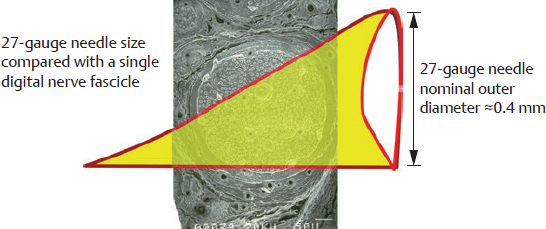

CHAPTER Many complications of upper extremity nerve decompressions initially present to the office as a patient inquiry about persistent or worsening paresthesias despite surgical decompression. In the early postoperative period, and with the absence of obvious infection, the most common provider response is undoubtedly that it should continue to improve with time. Unfortunately, there are complications that must be recognized for which interventions other than tincture of time are indicated to achieve the most optimal, long-term patient outcomes. There are many journal reviews related to the incidence, complications, and subsequent management of nerve compression syndromes; however, the actual incidence of complications is not as clear.1–5 Overall, reported incidence of nerve compression syndromes can be quite high. Carpal tunnel, for example, is reported to have a lifetime prevalence of 3 to 6%, making it the most common upper limb neuropathy and accounting for more than $500 million dollars of health care–related costs in the United States.1,6,7 Complications after carpal tunnel release are reported as 1 to 25%, with reoperation rates as high as 12%.8 Reported complications with cubital tunnel are similar, with reported complication rates of 3 to 20%.2,9 Additional nerve compression syndromes such as pronator syndrome, anterior interosseous nerve syndrome, posterior interosseous nerve syndrome, and Wartenburg’s syndrome (superficial radial neuritis) have much less published data for analysis of complication rates and subsequent reoperation rates. Overall the incidence of both nerve decompressions and complications is difficult to define, with wide reported ranges. This results in a potentially large number of compilations that must be accurately diagnosed and treated accordingly. Carpal tunnel release is worth noting specifically given its high reported incidence. With such a common presentation, it is no surprise that it is one of the most common outpatient, elective surgical procedures, with more than 500,000 surgeries performed in the United States each year.10 The procedure is often considered easy to perform; therefore many different surgical specialties perform it. The various methods for carpal tunnel release have been well described in the published literature, and complications associated specifically with median nerve decompression do not seem to be related to specific surgical approaches in most cases.11 However, complications of carpal tunnel release are reported to be as high as 25%.8 It is these complications that leave both the patient and surgeon with significant frustration. When things don’t go well after nerve decompression, a wrong diagnosis, an inappropriate operation, patient compliance, and unexpected events all become part of one’s thought process. This chapter focuses specifically on complications and deviations from the expected recovery course after upper extremity nerve decompression. Thorough and accurate preoperative assessment of any neuropathy is essential in determining the presence of nerve compression, the potential surgical indication, and the appropriate procedure. It is important not only to examine the entire length of nerves on patients with neuropathy but also to document clinical examination findings at the time of evaluation (Fig. 67.1). Later comparison and evaluation may be required in the event of either a complication or a slower than expected recovery. The most common compression neuropathy symptoms are numbness, tingling, dropping objects, positional triggering of symptoms, and waking at night with numbness. Findings on examination are Tinel’s sign, neuropathic pain, decreased sensibility, muscle wasting, positive provocative tests with pressure, or fulcrum stress.3,12 Ancillary testing such as nerve conduction, neurophysiological, and imaging studies and ultrasound can be useful when the diagnosis is complex or indeterminant. There is little consensus on the “gold standard” for upper extremity compression neuropathy, and many patients receive operations based on their history and clinical assessment. It is accepted that electrophysiology can provide additional support for a diagnosis, and in some insurance plans it is required before surgery is approved. Electrophysiological studies are especially helpful if complications arise after surgery.13 How ever, electrophysiology should also be considered when evaluating atypical presentations, “difficult patients,” and circumstances in which workers compensation or litigation are factors. Ultimately, when the patient is not progressing, the surgeon needs to delineate whether persistent or recurrent compression or other possible surgical complications, such as nerve laceration, injury to surrounding structures, or inaccurate original diagnosis, may have occurred. When the patient is unhappy and the outcome not as expected, the surgeon will be pleased to have accurately documented findings before surgery and had patient discussion regarding surgery and its potential complications. Summary Box Complications of Nerve Decompression Surgery • Injury to the palmar cutaneous branch of the median nerve • Injury to the recurrent motor branch of the median nerve • Injury to the medial antebrachial cutaneous nerve • Median nerve laceration • Ulnar nerve kinking • Ulnar motor branch injury during median nerve decompression • Incomplete median nerve release • Synchronous pronator or anterior interosseous nerve syndrome (AINS) • Posterior interosseous nerve compression • Unexpected and unsuspected diagnoses When physical examination and electrophysiological studies remain unclear regarding the site of compression or specific diagnosis, imaging should be considered. Narrowing, swelling, radiological signs of inflammation, and even nerve transection documented by imaging provide valuable information to the surgeon concerning preoperative diagnosis and postoperative complications. The advent of high-resolution ultrasound and magnetic resonance imaging (MRI) allow for more specific and reliable anatomical evaluation of nerves. Recent advances in ultrasound have added another evaluation tool for carpal tunnel syndrome (CTS) by evaluating the cross-sectional area of the median nerve through the carpal tunnel. Ultrasound imaging may provide additional benefit by identifying structural anomalies within the tunnel.14 Also described are using ultrasound-guided carpal tunnel releases and ulnar nerve releases as a potential method to reduce intraoperative nerve injury when using short-scar techniques.15–17 Additionally, some authors report that cubital tunnel syndrome can present with normal electromyography (EMG) and that ultrasound or MRI can aid in diagnosis if the clinical examination is not convincing.18 Overall, imaging is not necessary or the standard of care in the treatment of upper extremity nerve compression syndromes, but it can be a valuable tool in the presence of a broad differential diagnosis. Fig. 67.1 It is essential the entire peripheral nerve be examined, starting at the spinal cord and continuing the examination distally for both motor and sensibility functions. The rate of incomplete release is approximated at 9 to 23% for carpal tunnel,19–21 namely related to incomplete release of the distal flexor retinaculum. Incomplete cubital tunnel release resulting in revision has been reported, but there is limited data describing the incidence.22 Incomplete release for other upper extremity compression neuropathies is not well described. In our experience, accurate diagnosis and careful thorough decompression has not resulted in persistence or early recurrence. After release of a compressed nerve, if symptoms recur in the early postoperative period, persist, or become worse, incomplete nerve release and persistent compression should be strongly considered. Care should be taken to fully evaluate the patient for other causes of continued nerve symptoms despite release. If the likely cause of symptoms remains persistent compression rather than other sources, open decompression should be performed, and adjunctive procedures will probably be necessary. When reexploring a nerve that has had an injury, previous surgery adjacent to the nerve, or previous decompression, the surgeon must identify the nerve distal and proximal to the zone of previous surgery before exploring the area of concern. The surgeon should follow the nerve into the zone of injury from proximal and distal healthy nerve to assess, release, and resolve the nerve problem as appropriate. Directly approaching the nerve in the zone of previous surgery is likely to produce an injury to the nerve because of adjacent and adherent scar formation further complicating patient outcome and treatment. Once completely released, adjuvant procedures such as local vascularized pedicle fat flaps, venous tube wraps, collagen, or acellular dermal matrix wraps or transposition to a new position would be recommended. The term recurrent compression syndrome is usually reserved for individuals who have had nerve decompression surgery with symptomatic relief or significant improvement lasting for a period of months or years. In our experience, late recurrence is very rare and is most commonly observed in males with heavy repetitive work activities. After the symptom-free interval, progressive nerve compression clinical symptoms and worsening electrophysiological tests begin to occur. Patients presenting with these symptoms should have a thorough repeat evaluation from nerve root to end organs. The question then becomes whether this is a recurrence or an entirely new site of pathology. Clinical examination coupled with electrophysiology studies will help to further elucidate recurrent compression. Generally, when an entirely symptom-free period or dramatic improvement has occurred and the patient develops recurrent symptoms, it is appropriate to consider this as a recurrent compression. If recurrence is documented and the symptom-free interval is over a period of years, repeat nerve decompression is recommended. As with persistent compression, care should be taken to avoid injuring the nerve by careful proximal and distal exposure before exploring the area of concern. Usually only a decompression would be necessary; however, adjuvant procedures can be used depending on the specific findings and surgeon judgment at the time of exploration and release (such as a vascularized pedicle fat flap). The potential of antecedent synchronous pathology must be considered when evaluating a patient who is not improving. Although not a direct complication of surgical release, ideally the original evaluation would have discovered the synchronous pathology and considered additional treatment in conjunction with the original decompression surgery. When this is not the case, both the patient and physician can become frustrated with less-than-ideal outcomes after nerve decompression. Significant synchronous pathology that was undetected during preoperative assessment often leads to persistent symptoms after decompression. Pathology more proximal in the nerve distribution caused by compression, spinal foramen narrowing, thoracic outlet syndrome, demyelinating diseases, and syringomyelia are all reported as sites of synchronous nerve compression or pathology.23,24 As with other persistent nerve compression symptoms, imaging, nerve conduction velocity, EMG, and careful clinical examination can accurately determine nerve status. When evaluating a patient for perceived synchronous pathology as the cause for failure to improve, the surgeon should compare the new postoperative findings to those noted preoperatively. If synchronous pathology is a proximal or distal peripheral nerve compression, release at that compression site may improve symptoms if the nerve has not become irreversibly damaged. Preoperative undetected neuropathic disease like diabetes, demyelinating disease, and infectious disease are potential synchronous pathologies that may complicate or limit recovery. As with additional sites of compression, detection of neuropathy before operative release is ideal, because this can direct patient expectations after nerve release. If preoperative nerve conduction studies are available, the surgeon will be able to assess more accurately the severity, site, and management of the neuropathy. Fibrillation potentials, positive sharp waves, and conduction times that are very slow all point to pathology that may not completely recover after nerve decompression. When not recognized or not reported during an operation, occult direct nerve injury can be an initially frustrating and later a feared complication in follow-up visits. Direct nerve injury can be a result of patient positioning, thermal injury, crush injury, traction injury, injecting with large-caliber needles, direct suture of nerve, or cutting the nerve. Careful and attentive positioning will help to prevent temporary compression-related neuropathies secondary to prolonged, focal pressure or nerve stretch. Thermal injury can be minimized with the use of bipolar cautery. Care should be taken to retract and handle nerves with care to avoid traction or crush injury, and “Rope” retractors should not be used around the nerve. Adequate exposure and the use of operative loupes are indicated to ensure adequate identification and visualization of the nerve being decompressed, especially when the surgical site is fibrotic. When closing incisions, the surgeon must be careful to prevent injury to the nerve with a suture needle (Fig. 67.2) or strangulation of the nerve by including all or a portion of the nerve in the wound closure. The incidence of direct nerve injury is low for carpal tunnel release and is usually attributed to anatomical variations of the thenar motor branch of the median nerve.4,25 Similarly, iatrogenic injury to the ulnar nerve during cubital tunnel release has a low incidence, probably because fewer classes of surgeons release this nerve. In my experience, excessively short scars provide poor visualization unless an endoscope is used. In addition, the scissor “sliding” technique required with very short scar approaches puts the nerve being decompressed, as well as proximal nerve branches, at risk for laceration. Use of ultrasound guidance may improve safety. Many types of injury that do not involve direct nerve injury will improve with time. If the nerve does not improve and the Tinel’s sign does not progress distally, electrophysiology and careful clinical assessment should be able to isolate the site of nerve injury. When irreversible nerve injury is suspected, such as severe thermal injuries, crush injuries, or partial or complete nerve laceration, exploration and repair is indicated. If nerve transection or neuroma is discovered, the decision for neurolysis, resection of neuroma with direct repair, or resection of neuroma with nerve graft all require significant surgical judgment, intraoperative electrophysiogical capability, and microsurgical skills. The intervention choice should be performed according to the surgeon’s discretion based on preoperative assessment reinforced with intraoperative findings. The palmar cutaneous branch of the median nerve (PCBMN) originates from the median nerve 5 to 10 cm above the wrist crease and courses on the radial side of the palmaris longus tendon and third metacarpal shaft. An incision that is too radial to those landmarks risks injury to the PCBMN. The resulting hypothenar dysesthesia, combined with a hypersensitive neuroma, lead to a less-than-ideal outcome (Fig. 67.3). The recurrent motor branch of the median nerve (RBMN) is usually located distal to the transverse carpal ligament but may also be through the ligament. Always transecting the ligament adjacent to the hook of the hamate will prevent injury to the RBMN when it is anomalous in location (Fig. 67.4). Injury to the RBMN will lead to thenar muscle atrophy, loss of opposition, and weakness during key pinch functional activities. Fig. 67.2 It is essential to use small-caliber needles when injecting medications around peripheral nerves. The yellow triangle accurately represents the size of a 27-gauge needle. It is superimposed over a digital nerve fascicle. The 27-gauge sharp needle could easily transect an entire fascicle. An even larger needle could transect a small branch nerve or digital nerve. When injecting around nerves, small-caliber and tapered needles are ideal. Ultrasound-guided injections are also important for avoiding nerve injury during medication injection and when performing axillary nerve blocks for surgical anesthesia. The most commonly reported complication of cubital tunnel release is medial antebrachial cutaneous nerve (MABC) injury, kinking, and fibrosis. The incidence is reported to be between 5 and 15%.26 Should a patient present with injury to the MABC after cubital tunnel release, secondary exploration can be difficult because of dense perineural fibrosis surrounding the nerve. Injury to the MABC might also be associated with ulnar kinking because of inadequate release of the aponeurosis of the flexor carpi ulnaris or failure to remove the medial intermuscular septum (Fig. 67.5). MABC and kinking seem to be closely associated when secondary surgery is necessary. In these cases, surgical exploration should proceed with careful exposure of the nerve proximal and distal to the injury site to prevent inadvertent injury to the nerve.